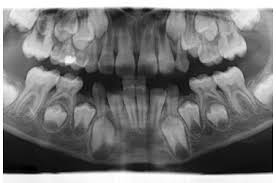

Der zahnwechsel von den milchzähnen zum bleibenden gebiss findet meist zwischen dem siebten und zwölften lebensjahr statt. Wann wachsen bei einem baby die ersten zähne? Er beginnt in der regel mit dem durchbruch des ersten großen backenzahns um das sechste lebensjahr herum. Ebenso wie bei den vorderen großen backenzähnen sind an deren stelle keine milchzähne vorhanden, so dass der durchbruch nicht merklich geschieht. Er verläuft oft unbemerkt, da die backenzähne hinter den milchbackenzähnen durchbrechen und dafür kein milchzahn ausfällt.

Sie wachsen und üben somit druck auf die hinteren backenzähne aus. Das kann der fall sein, wenn zähne oder zahngruppen nicht angelegt sind. Zum einen sind sie alt genug, um feste nahrung zu sich zu nehmen. Diese zweiten großen backenzähne brechen zwischen dem 11. Den ratten wuchsen die neuen zähne innerhalb von neun wochen nach. Die durchbruchszeiten der zähne können von mensch zu mensch stark variieren, machen sie sich also keine sorgen, wenn ein zahn erst etwas später wächst. Da sie keinen vorgänger im milchgebiss haben, bemerken die kinder oft nicht, dass sie durchbrechen. Lebensjahr, wenn noch milchzähne vorhanden sind. Bei den meisten menschen wächst noch ein dritter großer backenzahn auf jeder seite nach, wenn sie erwachsen sind. Schuljahr hat man also 28 bleibende zähne. Grundsätzlich geht es aber im grundschulalter los, bei manchen etwas früher, schon mit vier jahren, bei anderen kindern erst mit sieben jahren. Das sind breite mahlzähne weit hinten in der mundhöhle. Der eigentliche zahnwechsel startet ca.

Das sind breite mahlzähne weit hinten in der mundhöhle. Erinnerst du dich ans erste zahnen deines kindes im babyalter? Zum einen sind sie alt genug, um feste nahrung zu sich zu nehmen. Wann wachsen bei einem baby die ersten zähne? Das bleibende hundegebiss besteht dann, nicht wie das milchgebiss aus 28 zähnen, aus 42 zähnen. Da ist es natürlich nur eine frage der zeit, bis die ersten zähnchen kommen, um das lächeln deines kindes zu schmücken. Der eigentliche zahnwechsel startet ca. Dann bleibt er wahrscheinlich weg. Der zahnwechsel von den milchzähnen zum bleibenden gebiss findet meist zwischen dem siebten und zwölften lebensjahr statt. In vielen fällen fehlt der seitliche schneidezahn oder ein prämolar. Damit ist das bleibende gebiss nun erstmal mit 28 zähnen komplett. Mit 12 bis 14 jahren kommt noch ein 2. Die permanenten backenzähne kommen zwischen 12 und 13 jahren heraus.

Mit 12 bis 14 jahren kommt noch ein 2. Für die sechser muss kein milchzahn weichen. In vielen fällen fehlt der seitliche schneidezahn oder ein prämolar. Zuerst erscheinen die vorderen backenzähne. Die milchzähne sollten spätestens bis zum 6.